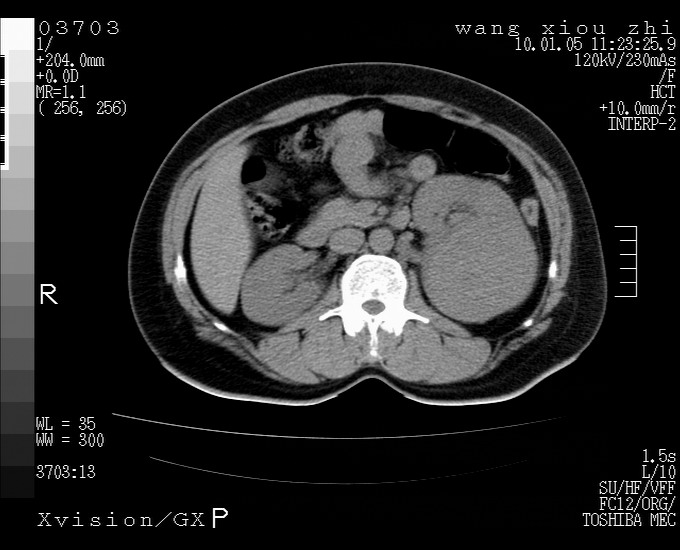

标题: CT23996:f,40.B超提示肿物。 [打印本页]

标题: CT23996:f,40.B超提示肿物。

左肾体积增大!下极见一密度略高团状软组织影!肾周结构组织未见明显异常!考虑左肾占位!建议增强!病史?

左肾占位性病变,建议增强。

左肾占位性病变,考虑肾癌,建议增强 。

左肾占位,肾门及腹膜后淋巴结肿大,考虑透明细胞癌可能性大,建议增强

左肾体积增大,内见肿块影,考虑占位,建议增强。